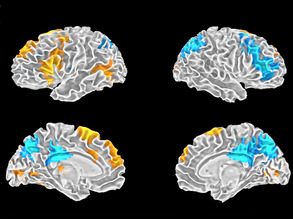

Monkey Magic

07